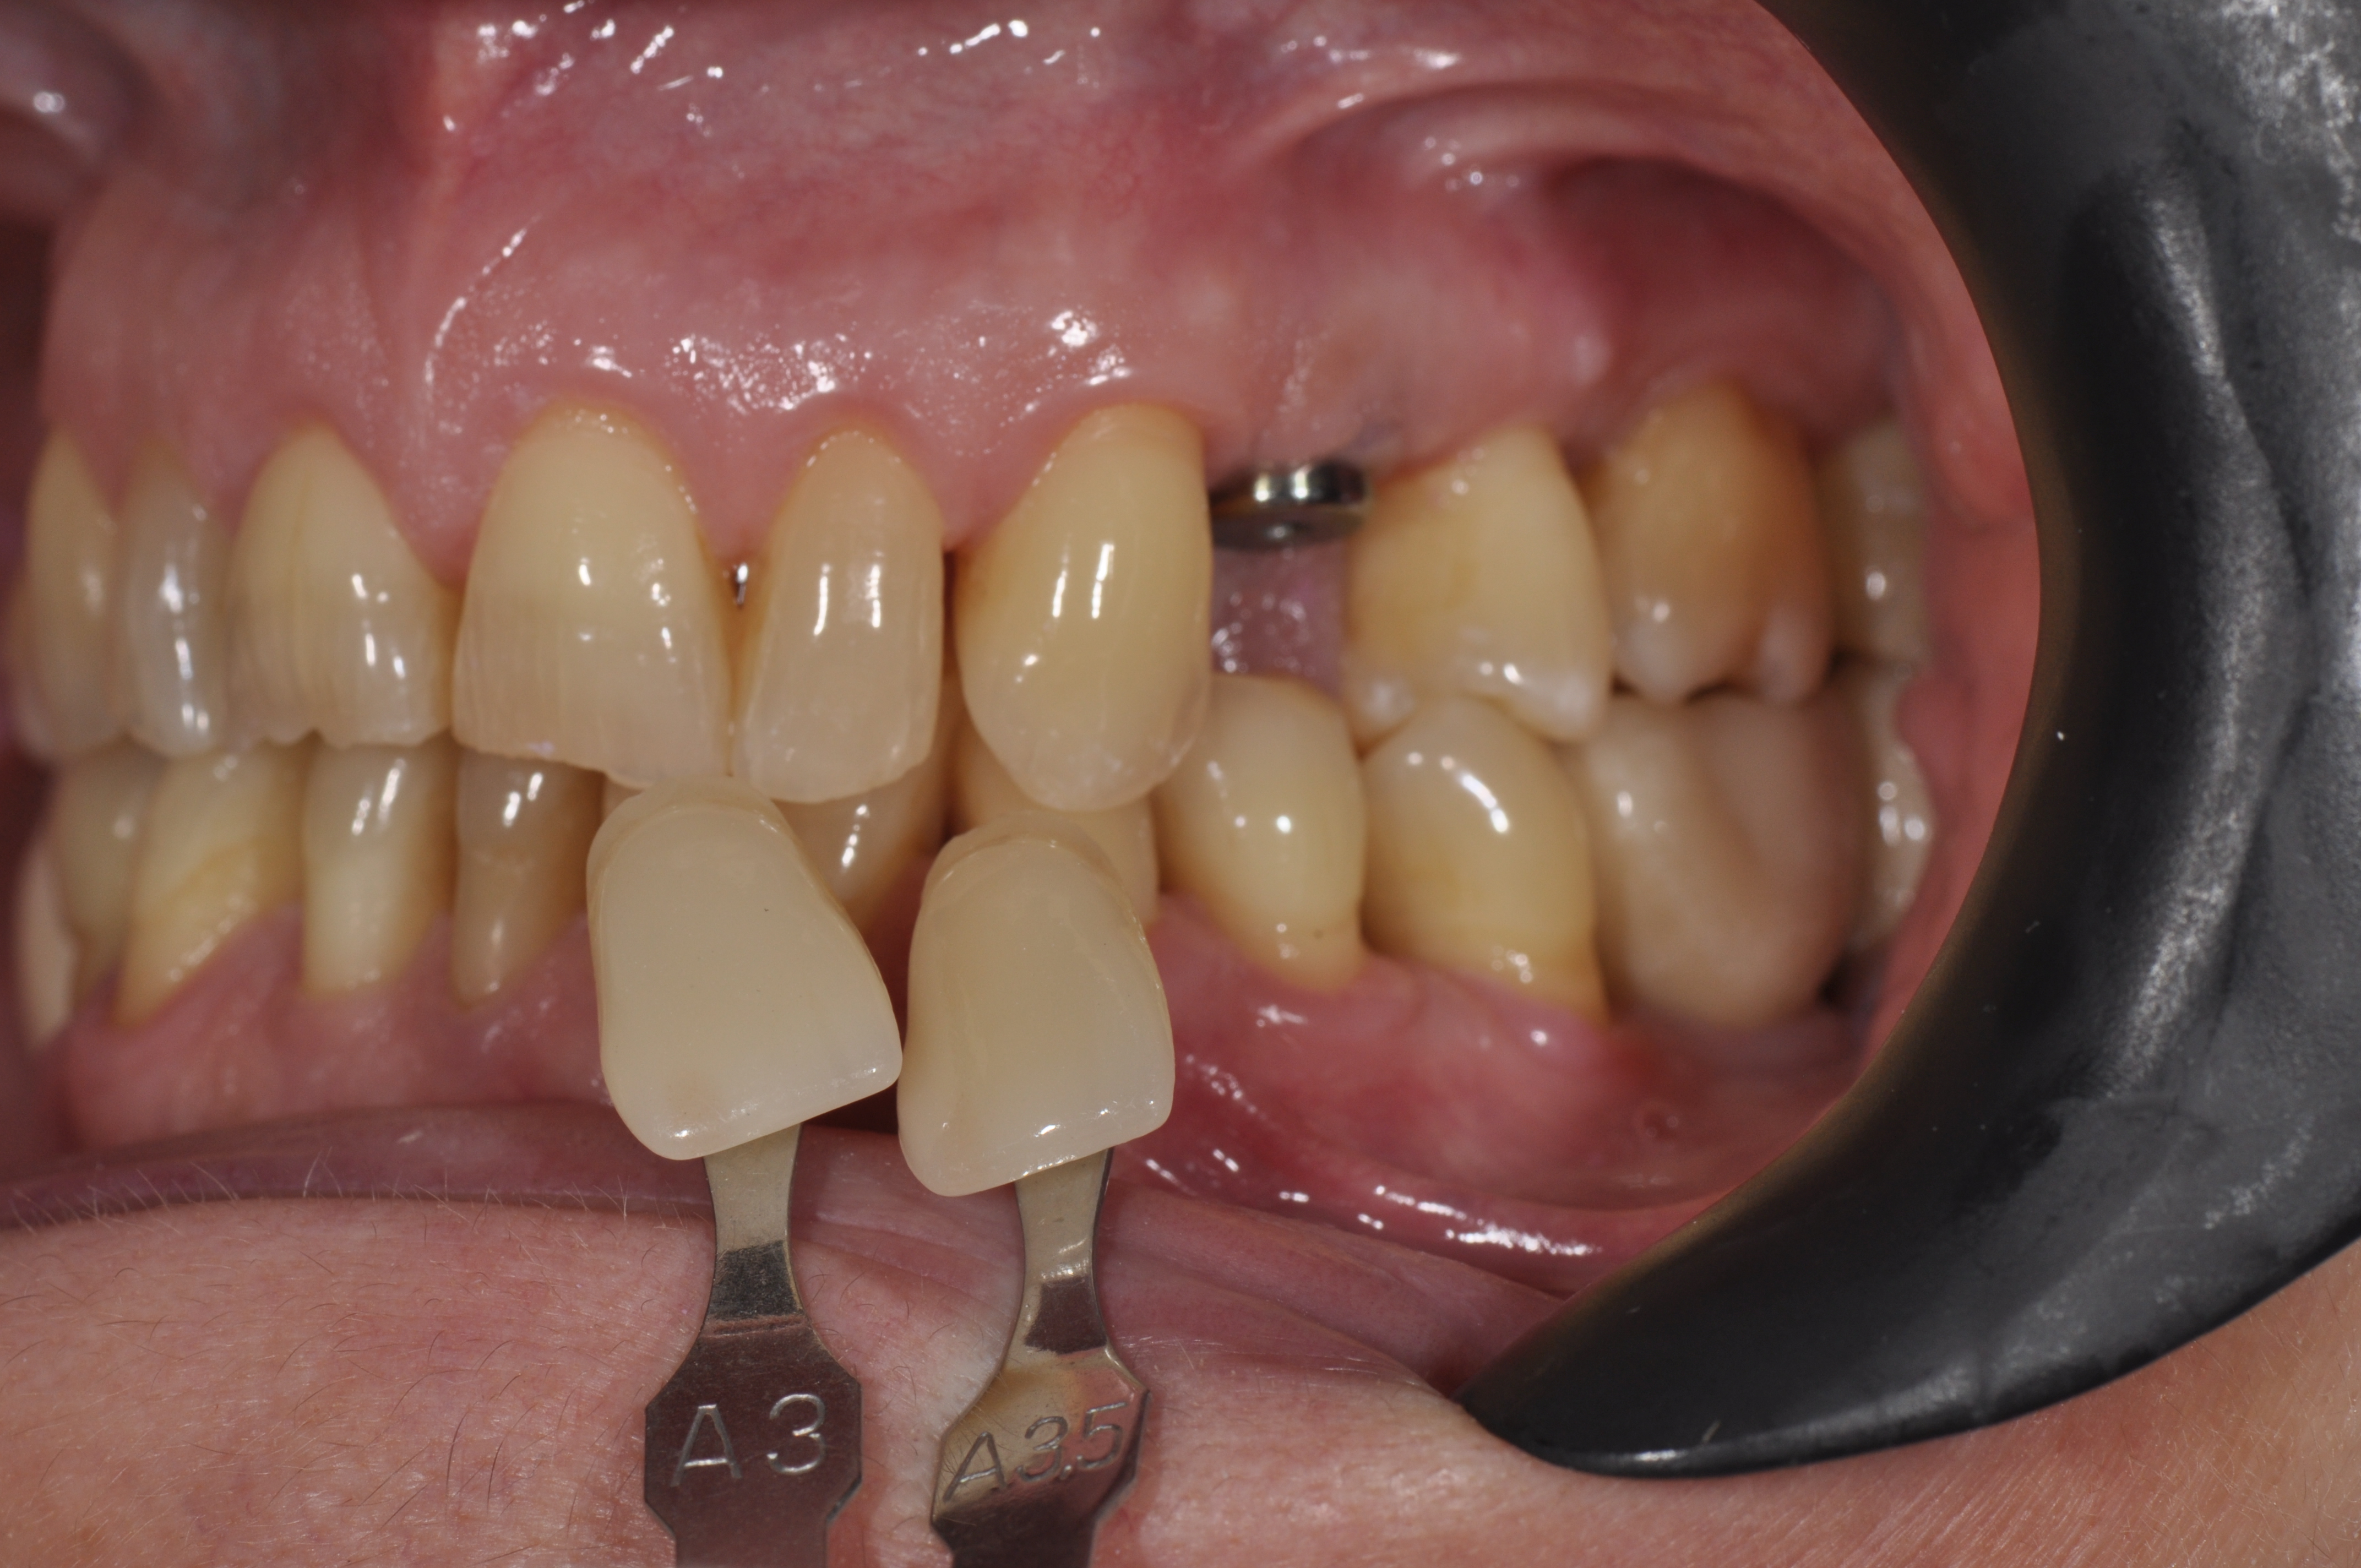

Prótesis Dental en Segovia

En Clidentse, el Dr. César Segovia Miguel es quien se encarga de la especialidad de prótesis Fija o Removible, tanto sobre diente, como prótesis sobre Implantes. Porque tu salud bucodental es nuestra prioridad, queremos hacer de tu tratamiento una experiencia positiva.

Implantes e implantoprótesis en Segovia

Es la especialidad dedicada a reponer los dientes perdidos/ausentes mediante la colocación de un implante, un “tornillo” de titanio anclado al hueso, y que una vez se ha osteointegrado (soldado al hueso), permite colocar una corona protésica atornillada directamente al implante.

En Clidentse contamos con el Dr. Ángel Silmi para esta especialidad, que es sin duda la opción ideal y más conservadora para reponer los dientes perdidos y/o ausentes. De otra forma, la prótesis fija convencional sobre

diente exige tallar (desgastar) los dientes adyacentes a la ausencia, los cuales hacen de pilares de un puente de 3 piezas para reponer el diente perdido. Con los implantes dentales, esta antigua opción terapéutica fija está desaconsejada. Hoy día se tiende a hacer una Odontología Mínimamente Invasiva. Y tallar los dientes supone un tratamiento excesivamente traumático y debilitante. La resistencia de los dientes está relacionada directamente con la cantidad de diente sano remanente.